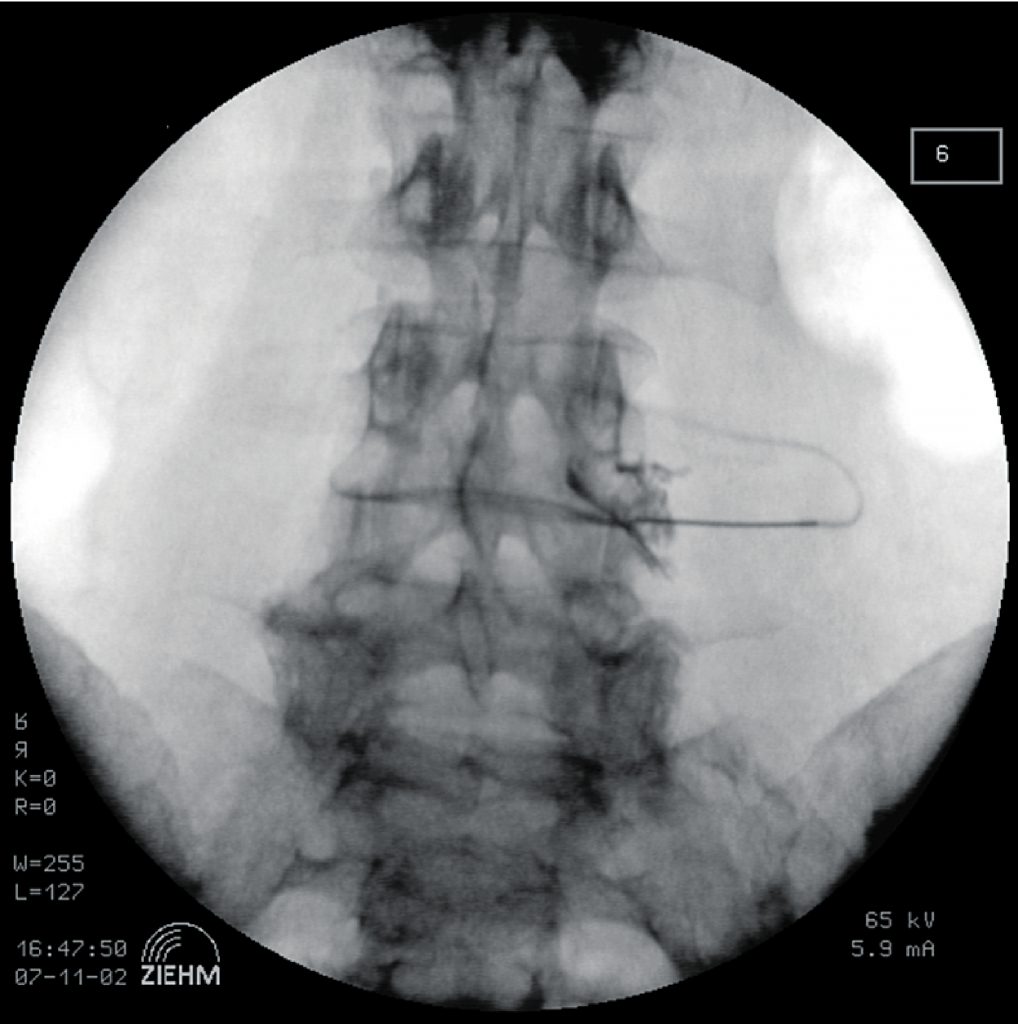

Zur Diagnostik werden aufgrund der hohen Rate falsch-positiver Ergebnisse bei der ersten Intervention zwei Interventionen zu unterschiedlichen Zeitpunkten, sinnvollerweise mit unterschiedlich lang wirkenden Lokalanästhetika (zum Beispiel Lidocain und Bupivacain) durchgeführt (11). Vor Injektion des Lokalanästhetikums wird zur definitiven Lagekontrolle sowie zum Ausschluss einer intravasalen Position der Nadelspitze Röntgenkontrastmittel injiziert (Abb. 1). Nach positiver Diagnostik kann unter therapeutischem Aspekt sowohl die perkutane funktionelle Denervation (Radiofrequenztherapie) als auch die transforaminale Steroidinfiltration zum Einsatz kommen, wobei die Durchführung grundsätzlich der Durchführung der diagnostischen Blockaden sehr ähnlich ist. Für die Wirksamkeit der Radiofrequenztherapie besteht etwas Evidenz (12), die Evidenz bezüglich Steroidinfiltrationen ist nicht eindeutig belegt (13).